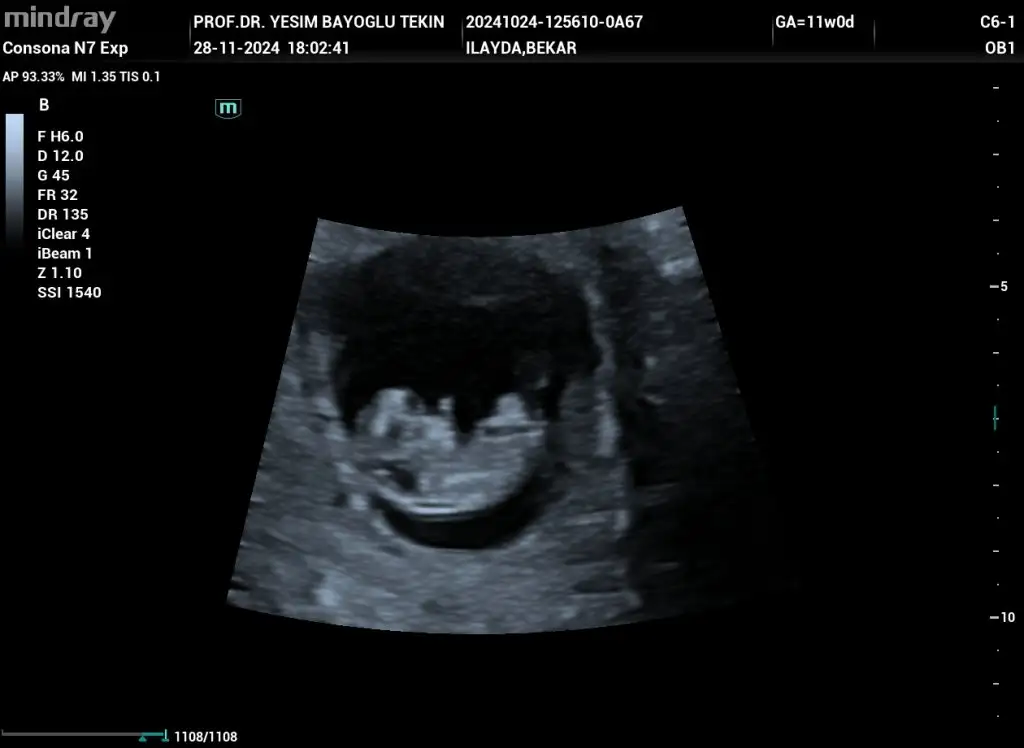

Merhaba 10 haftalık cinsiyet tahmini yapabilir misiniz rica etsem

• IMG-20241128-WA0014.webp

IMG-20241128-WA0014.webp

21,7 KB · Görüntüleme: 32

• IMG-20241128-WA0011.webp

IMG-20241128-WA0011.webp

31,8 KB · Görüntüleme: 31

• IMG-20241128-WA0008.webp

IMG-20241128-WA0008.webp

19,4 KB · Görüntüleme: 37